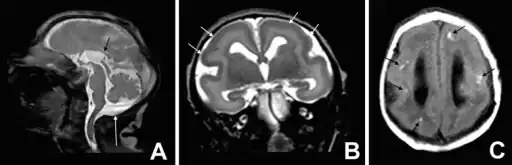

Diagnosis

Microlissencephaly can be diagnosed by prenatal MRI.[30] MRI is better than ultrasound when it comes to detecting microlissencephaly or MSGP prenatally.[34] The ideal time for proper prenatal diagnosis is between the 34th and 35th gestational week which is the time when the secondary gyration normally terminates. In microlissencephaly cases, the primary sulci would be unusually wide and flat while secondary sulci would be missing.[35]

At birth, lissencephaly with a head circumference of less than minus three standard deviations (< –3 SD) is considered microlissencephaly.[36]